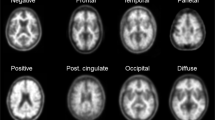

Visual interpretation

The PiB PET images generated through the QC process above were independently interpreted visually by three expert raters blinded to the clinical category. Information about age, sex, and T1-weighted MRI images was provided to the raters. In the visual interpretation, the raters evaluated the regional PiB uptake for each of four cortical areas on each side (frontal lobe, lateral temporal lobe, lateral parietal lobe, and precuneus/posterior cingulate gyrus) as positive, equivocal, or negative regional uptake, the definitions of which were as follows: positive, uptake is clearly higher than in cerebral white matter that covers more than one gyrus of the cerebral cortical area; equivocal, uptake is slightly higher than or similar to that in cerebral white matter that covers more than one gyrus of the cerebral cortical area, i.e., radioactivity extending beyond white matter to the cortical surface, or a high uptake spot limited to one gyrus; and negative, uptake is lower than in cerebral white matter in any region of the cerebral cortex. Of the total scans in J-ADNI, 91.3% of the visual assessments were matched among the three raters (Cohen kappa = 0.88). After independent interpretations, consensus reading was performed to determine the unified visual interpretation for each PET image by the three raters and two other experienced discussants [10]. The unified visual interpretation stored in the J-ADNI was used for this study.

Figure 2 shows the time courses of SUVRs grouped by visual assessment and by clinical category. In the amyloid-negative CN group, the upper confidence limit of the 97.5 percentile for the baseline SUVR was 1.20. Most SUVRs in the amyloid-negative group (LMCI, ADD) remained below this level. In the amyloid-equivocal group, no evident differences in the longitudinal trends of SUVR were observed among the CN, LMCI, and ADD groups. In the amyloid-positive group, all individual values remained above SUVR 1.3, indicating a clear difference in the distribution of the SUVR between the amyloid-positive and amyloid-negative groups. In the visually amyloid-positive group, the annual changes in the SUVR were 0.04 ± 0.04 in the CN group, 0.04 ± 0.07 in the LMCI group, and 0.03 ± 0.07 in the ADD group. The SUVRs in the amyloid-positive CN group tended to increase over time from a lower baseline SUVR compared with the LMCI and ADD groups. Conversely, no evident differences in the longitudinal trends of SUVR were observed among the LMCI and ADD groups. In the visually amyloid-positive group, 19 individuals showed a decreasing SUVR (CN n = 1, LMCI n = 8, ADD n = 10). The baseline SUVR in these individuals was significantly higher than the baseline SUVR of all visually amyloid-positive individuals (2.10 ± 0.33 vs 1.86 ± 0.31, p = 0.003).

Individual longitudinal changes in SUVR during the 3-year follow-up. Scatterplots show the SUVR at baseline and in the 3-year follow-up. The dotted line shows the SUVR threshold of 1.20 derived from the upper confidence limit of the 97.5 percentile for the baseline SUVR in the amyloid-negative CN group. Negative PiB visually amyloid-negative, Equivocal PiB visually equivocal, Positive PiB visually amyloid-positive, ΔSUVR the annual change in the SUVR

In individuals evaluated as visually amyloid-negative, their SUVRs remained within the 97.5 percentile of the baseline SUVR over time. This finding was observed regardless of the clinical categories of CN, LMCI, and ADD (Fig. 2). Barring a few exceptions, individuals with an amyloid-negative image showed no trend towards a gradual increase in the SUVR. In the amyloid-negative group, very few individuals showed an upward trend in the SUVR. Similar cases have been found in other longitudinal cohorts [4, 35], suggesting that they may represent the very early stage when amyloid accumulation has turned upward. On the other hand, individuals with a visually amyloid-positive image showed a time course with an SUVR of 1.3 or higher. The SUVR in the visually amyloid-positive group showed a gradual increase with a few exceptions. This was consistent with previous studies that reported [4,5,6,7, 36, 37] that when a cut-off value of SUVR or distribution volume ratio dividing low and high accumulation was used, the high accumulation group showed a gradual increasing tendency above the cut-off value, and the low accumulation group did not show an increasing tendency under the cut-off value. These findings suggest that the risk of progression of amyloid accumulation is low in the visually-negative group, whereas the visually-positive group is at an increased risk as well as SUVRs.